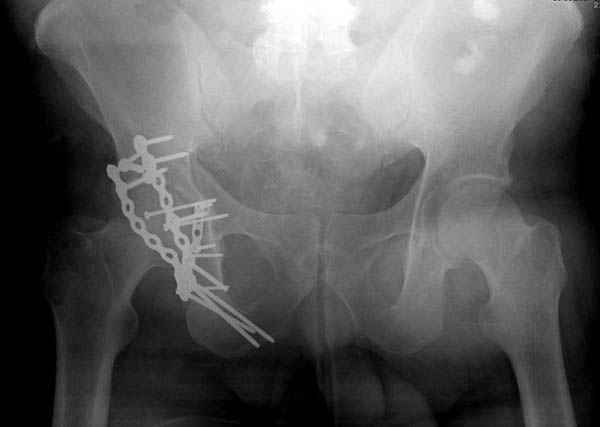

Второй случай, для лечения перелома проксимального

плеча применили пластину "Hand Innovation"

Пластина имеет преимущества перед другими "Locking

Implants", потому что пластину можно уложить намного ниже чем другие пластины и имеется возможности проведения шурупов под 130 градусным углом, таким образом можно уменьшить операционный разрез в проксимальной части.

Прооперирован вчера на 13 день после поступления.

Больному 41 и из-за гемодинамической нестабильности в течение первых 7 дней был в реанимации под интубационной седацией.

Кроме перелома плеча у больного старый дистракционный перелом T12-L1 оперированный когда-то и кем-то, открытый перелом костей предплечья, который был прооперирован в ночь поступления, после I&D (хирургической обработки). Из-за разрыва селезенки при поступлении травма хирургами произведено удаление.

Дополнительно имеется перелом ацетабулума: задняя

колонна с полупоперечным переломом, и переломы костей лица.

На седьмой день зафиксирован перелом ацетабулума через задний доступ. Перед операцией для профилактики DVT, IVC фильтер, также получает Lovenox.